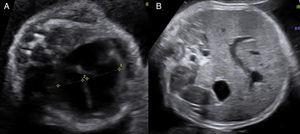

En el estudio ecográfico fetal se visualizó un feto de sexo femenino que presentaba una micromielia severa (fig. 7), a expensas de un acortamiento grave de todos los huesos largos. Además presentaba una hipomineralización de la calota fetal, que se veía tanto en el corte medio sagital como en los cortes axiales, objetivándose los huesos de la calota finos, que permiten una clara visualización de las estructuras encefálicas y que al presionar con el transductor sobre la misma se deprimen (fig. 8). El tórax estaba hipoplásico, con una cardiomegalia relativa y desproporción toracoabdominal, con ratio de 0,55 (fig. 9).

A y B) Corte axial del tórax fetal, se visualiza un tórax pequeño con caja torácica estrecha y corazón de tamaño normal pero que impresiona de mayor tamaño por lo que se diagnostica de hipoplasia torácica con cardiomegalia relativa. C) Corte longitudinal del tórax fetal. Se objetiva un tórax pequeño en relación con el abdomen fetal.